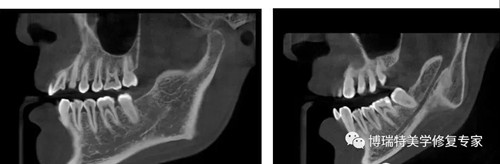

智能3D全景由外向内33张全景片观查

普通全景图(同一患者前牙区埋伏牙观察)